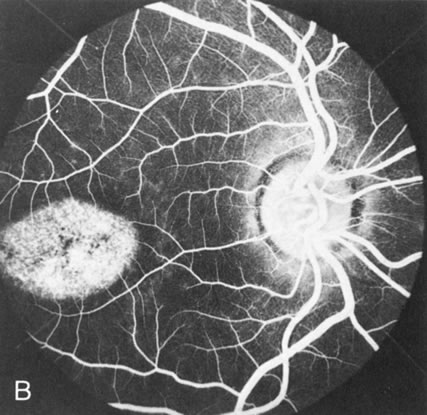

Dye leakage in RP may occur from the retinal vessels or at the level of the retinal pigment epithelium (Fig. 1B).2–4 The leakage may be seen in the macula and posterior pole, along the vascular arcades in the distribution of the radial peripapillary capillaries, and in the periphery (where an exudative vasculopathy resembling Coats' disease is suggested).